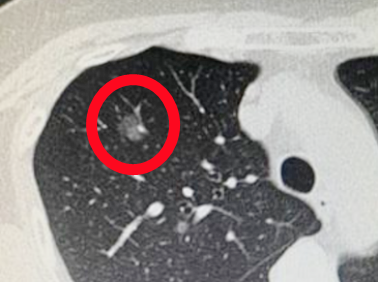

病例1:胸部摄片未见明显异常,但CT扫描发现肺上叶磨玻璃密度结节,

术后病理检查:微浸润腺癌

摄片(DR)是X线透过人体后投射到采集板上所形成的图像,是二维叠加图像,肺部早期病变(尤其是我们最关心的恶性肿瘤)完全可能被肋骨、心影、甚至胸壁软组织所重叠干扰。所以在我们实际工作中发现,当摄片都发现肺部肿瘤了,大部分都是中、晚期,失去了彻底治愈的可能。所以摄片报告上写未见异常,不一定真无异常。